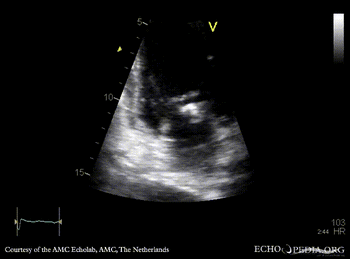

Endocarditis of mitral valve

A3CH: vegetations on AMVL A2CH